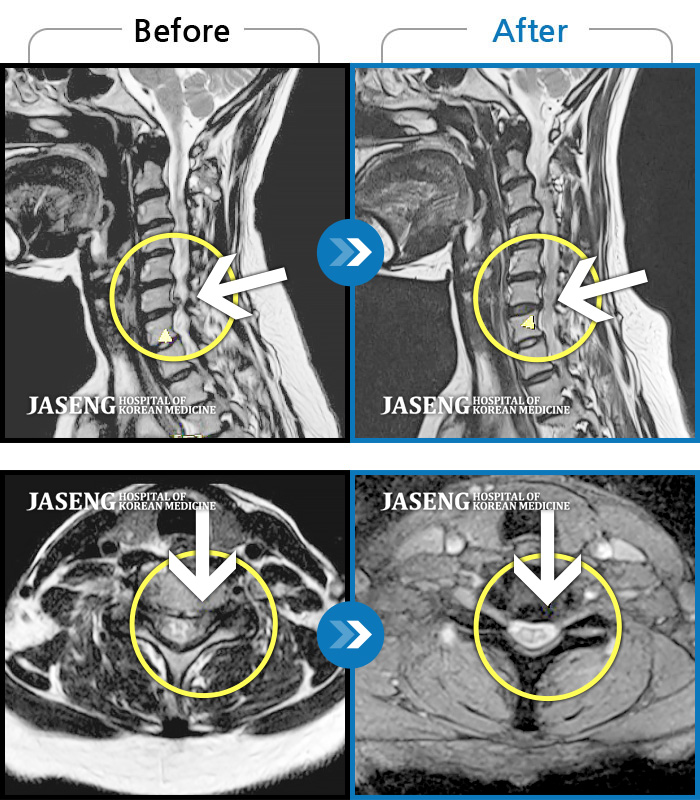

자생 비수술 한방통합치료 후

터진디스크가 흡수된 모습

양측 후경부 부터 견갑골 내연까지 이어지는 묵직한 통증

2020.09.10 ~ 2022.08.18